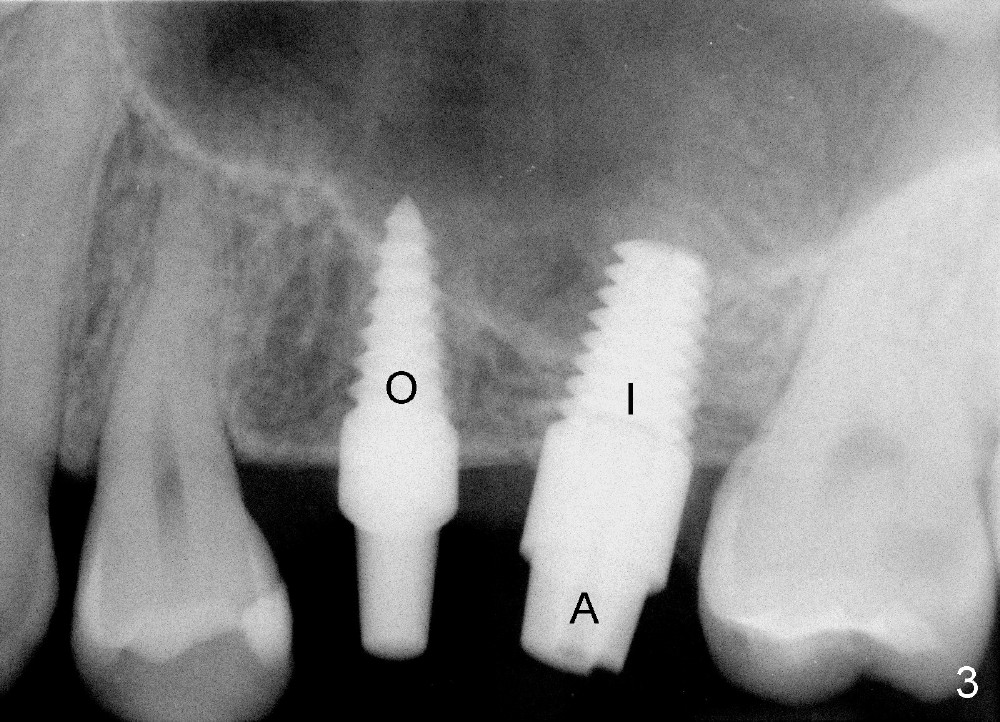

The patient returns for #13,14 implant placement. The ridge appears to be wide buccolingually (Fig.1 mirror view). A 4 mm tissue punch is used for access at the sites of #13 and 14. Osteotomy is initiated by using 3 mm trephine bur at the depth of 4 mm at both sites; 2 mm pilot drill is used to continue osteotomy at 8 mm deep at the site of #13. Sinus lift is accomplished by using tapered osteotomes 2,3 mm 6 mm deep, followed by 4.5x11 mm tap (Fig.2 T); 2 mm pilot drill (P) is reinserted into #13 osteotomy site with inadvertently penetrating the sinus floor. When the tap is removed from the site of #14, the sinus membrane is also found to be perforated. The sinus membrane at both sites is repaired by insertion of collagen dressing before bone graft. A 4x11 mm one-piece implant is placed at the site of #13 slowly hoping that it does not re-perforate the sinus membrane (Fig.3 O). Due to limited restorative height, the abutment portion of the one-piece is expected to be trimmed (Fig.4 O). In case of implant complication or failure, the implant may be difficult to be removed. Therefore the implant at the site of #14 is two piece one (Fig.4,5 I/A, 5x11 and 4x3 mm, respectively). The insertion torques for #13 and 14 are 35/40 and >60 Ncm. Immediate provisionals are canceled mainly because of patient's inability to open wide for long. Perio dressing is placed instead after adjustment of the height of the abutments. The patient experiences one episode of light nasal hemorrhage a few hours postop. Although the patient takes Amoxicillin for 1 week periop, the implant at the site of #13 dislodges 1 months postop (Fig.5). Immediate re-placement with a larger 2 piece one is canceled because of mild infection mesiobuccal to the implant at the site of #14 (Fig.6 >). Exploration around the latter implant reveals possible thread exposure in a small area. After copious irrigation with normal saline, Arestin is placed. Two months post exfoliation, the site is re-entered (Fig.7,8). There is a lingual defect. Osteotomy is initiated as buccal as possible. A 4.5x11 mm tapered tap penetrates the sinus floor without tearing the membrane (Fig.9). The same-sized implant is placed (25/30 Ncm) with sinus lift (Fig.10 *). The lingual defect is bone grafted. There is dehiscence lingually 7 days postop (Fig.11). Impression for final restoration is taken 1.5 months postop because of pending wedding. The crown has been in function for 2.5 months.